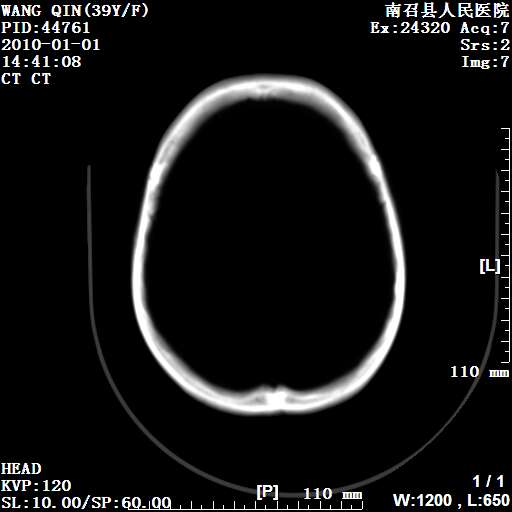

以下是引用随光逐影在2010-1-22 9:03:00的发言:[br]考虑左侧中颅窝(蝶骨翼区)脑膜瘤侵犯蝶骨翼并突入左侧眼眶。

以下是引用水过无痕在2010-1-22 14:55:00的发言:[br]一、定位:颅外占位;二、定性:恶性可能性大;三、组织来源:来源于左侧眼外直肌或其他部位;考虑为:横纹肌肉瘤>转移瘤>脑膜瘤.